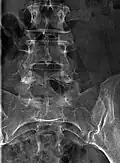

Occulta bedeutet „verborgen, nicht sichtbar“. Diese Form der Spina bifida ist dadurch gekennzeichnet, dass sich nur ein zweigespaltener Wirbelbogen findet, ohne dass das Rückenmark mit seinen Rückenmarkshäuten (Meningen) beteiligt ist. Sie ist darum nicht von außen sichtbar. Die Spina bifida occulta ist recht häufig und wird oft nur zufällig bei Röntgenaufnahmen oder einer Untersuchung des Rückens festgestellt. Besonders bei bettnässenden Kindern wird die Spina bifida occulta auffallend häufig gefunden. In der Regel hat sie medizinisch keine besondere Bedeutung; eine Behandlung ist nicht nötig. Ein Dermalsinus kann vorkommen.

Die Spina bifida occulta wird in der Regel nur zufällig festgestellt.